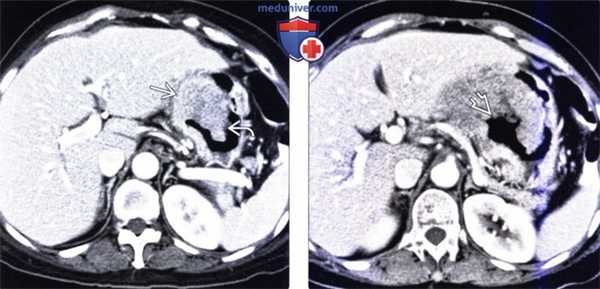

(Слева) На аксиальной КТ с контрастным усилением визуализируется экзофитное объемное образование мягкотканной плотности, деформирующее дистальные отделы желудка и двенадцатиперстную кишку.

(Справа) На аксиальной КТ с контрастным усилением у этого же пациента определяется быстрое контрастное усиление образования с наличием участков некроза; визуализируются также отчетливо выделяющиеся сосуды, участвующие в его кровоснабжении.

(Слева) На аксиальной КТ с контрастным усилением вдоль малой кривизны желудка определяется полиповидное объемное образование, имеющее плотность, соответствующую мягким тканям. Поскольку значительная часть образования в этом случае располагается в просвете желудка дифференциальная диагностика с раком является затруднительной.

(Справа) На аксиальной КТ с контрастным усилением у этого же пациента визуализируется большая зона кавитации внутри образования, сообщающаяся с просветом желудка.